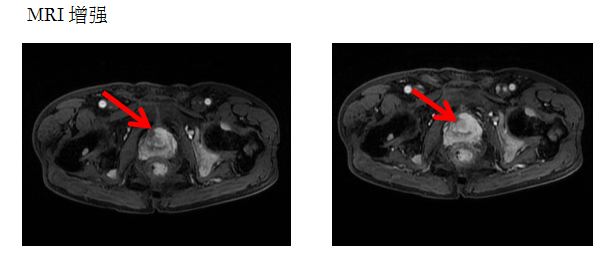

患者何大爷,最近出现尿频、排尿疼痛,肉眼血尿等症状。于是到医院检查,报告上显示“PSA”升高,115.15ng/mL。医生建议做个前列腺增强磁共振。

异常增大的前列腺,增强后呈不均匀明显强化并可见盆腔多发淋巴结转移及骨质破坏。